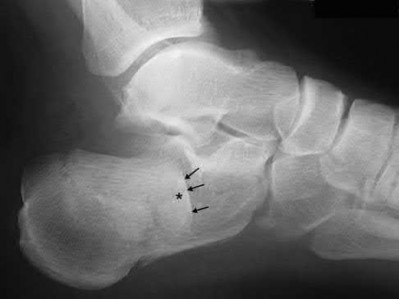

Figure 28 is the lateral radiograph of a patient who sustained an intra-articular fracture of the calcaneus. The structure (*) depicted by the arrows most likely represents which osseous component of the calcaneus?

Lateral portion of the posterior facet Corrent answer: 5

Fractures of the calcaneus occur as a result of shear and compression forces. Foot position at the time of impact, the force of the impact, and bone quality all dictate the degree of comminution and fracture line orientation. Two primary fracture lines are consistently observed, one of which divides the calcaneus into medial and lateral portions. An essential feature of this fracture

line is that it creates a fragment (sustentaculum tali) that remains attached to the talus by the interosseous ligament. This medial portion (constant fragment) of the posterior facet retains its normal anatomic position beneath the posterior talus. Its corresponding lateral component (labeled with an * in the figure), however, can be found displaced inferiorly within the body of the calcaneus. It is often rotated 90 degrees (as depicted in Figure 28) in relation to the remainder of the subtalar joint. This gives the appearance of what has been described as the "double-density" sign. The middle facet is more anterior and less commonly displaced. The lateral wall is nonarticular.